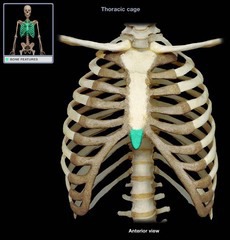

sterum

29

New cards

Sternum body

30

New cards

sternum manubrium

31

New cards

sternum xiphoid process